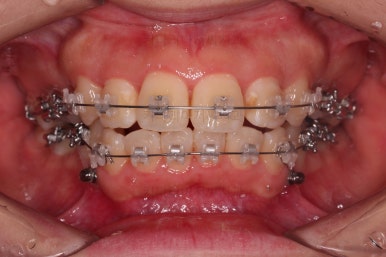

부산무턱교정치과 초진 시 입안의 모습입니다.

전반적으로 치열이 삐뚤고요. 아랫니가 윗니보다 뒤쪽으로 많이 가려져 있죠.

그래서 앞에서 봤을 때 아래 앞니가 거의 보이지 않는 상태인데요.

이런 교합을 "과개교합"이라고 표현합니다.

전반적인 교합, 치열, 과개교합, 튀어나와 보이는 앞니 등을 개선해줘야겠네요.